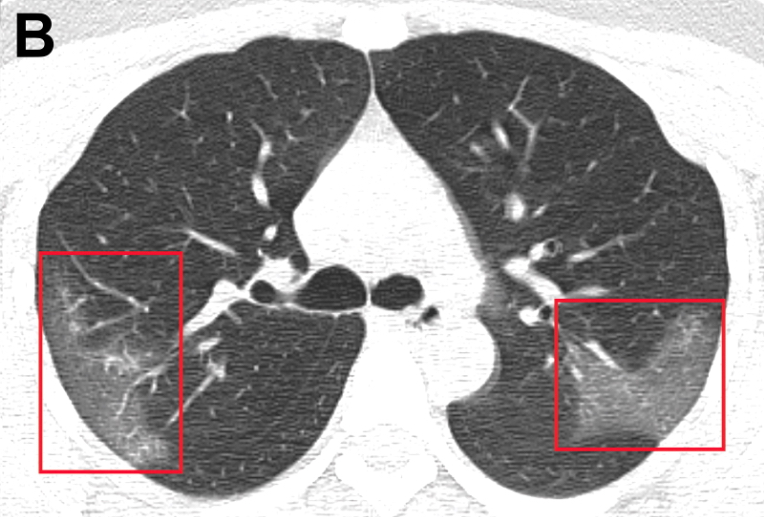

Características del cuadro de daño pulmonar asociado al cigarrillo electrónico

Casi la mitad de los 160 casos estudiados en California requirió internación en UTI y un 29% tuvo asistencia respiratoria. La asociación más frecuente fue con productos de cannabis de fuentes informales y en el 84% de los casos contenían vitamina E. JAMA Internal Medicine, 6 de marzo de 2020.